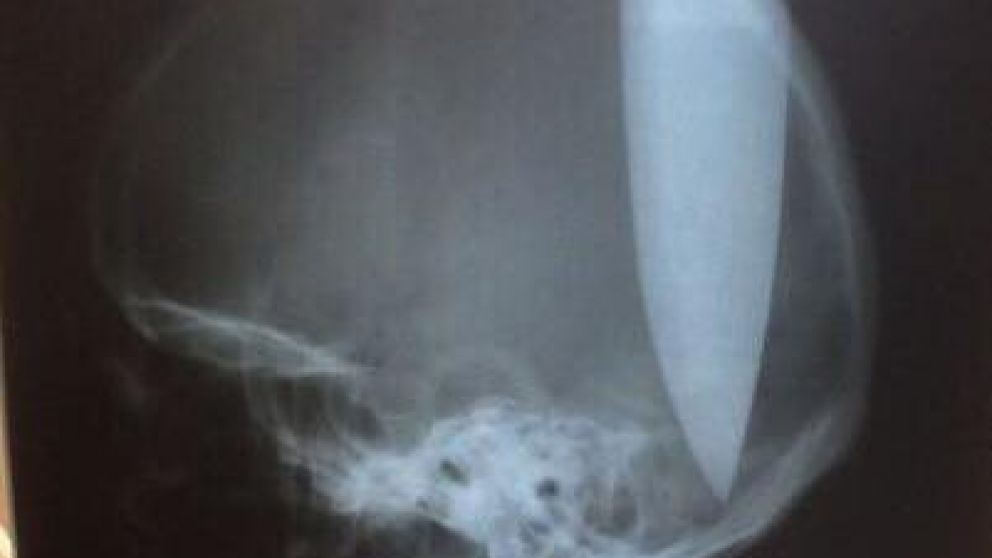

Un hombre con aparentes trastornos psiquiátricos se clavó un cuchillo de 20 centímetros en su cabeza como "remedio" casero contra un resfriado.

El individuo explicó a la policía que decidió clavarse el cuchillo para que su cabeza "pudiera respirar" porque sufría congestión nasal a causa de un fuerte resfrío.

El herido fue llevado de urgencia a un hospital, donde se le extrajo el cuchillo. El paciente se encuentra estable, fuera de peligro, aunque permanecerá internado en terapia intensiva, al menos, una semana.